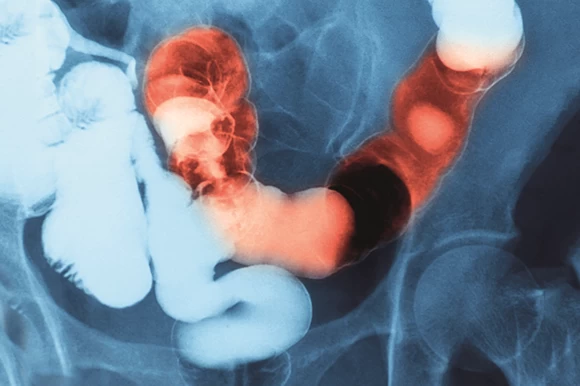

Φλεγμονώδεις νόσοι του εντέρου: Για ποιες ψυχικές παθήσεις αυξάνουν τον κίνδυνο

Οι Ιδιοπαθείς Φλεγμονώδεις Νόσοι του Εντέρου (ΙΦΝΕ) είναι η Ελκώδης Κολίτιδα και η Νόσος Crohn. Πρόκειται για ανίατες χρόνιες παθήσεις του γαστρεντερικού συστήματος με παρόμοια συμπτώματ...